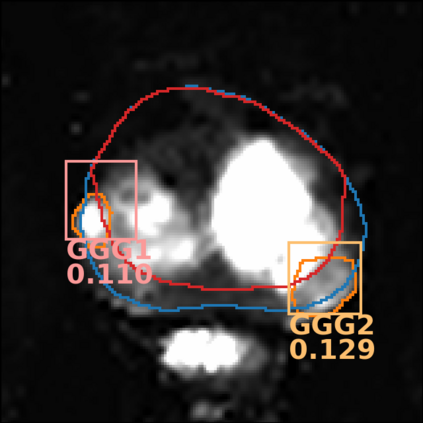

The emergence of multi-parametric magnetic resonance imaging (mpMRI) has had a profound impact on the diagnosis of prostate cancers (PCa), which is the most prevalent malignancy in males in the western world, enabling a better selection of patients for confirmation biopsy. However, analyzing these images is complex even for experts, hence opening an opportunity for computer-aided diagnosis systems to seize. This paper proposes a fully automatic system based on Deep Learning that takes a prostate mpMRI from a PCa-suspect patient and, by leveraging the Retina U-Net detection framework, locates PCa lesions, segments them, and predicts their most likely Gleason grade group (GGG). It uses 490 mpMRIs for training/validation, and 75 patients for testing from two different datasets: ProstateX and IVO (Valencia Oncology Institute Foundation). In the test set, it achieves an excellent lesion-level AUC/sensitivity/specificity for the GGG$\geq$2 significance criterion of 0.96/1.00/0.79 for the ProstateX dataset, and 0.95/1.00/0.80 for the IVO dataset. Evaluated at a patient level, the results are 0.87/1.00/0.375 in ProstateX, and 0.91/1.00/0.762 in IVO. Furthermore, on the online ProstateX grand challenge, the model obtained an AUC of 0.85 (0.87 when trained only on the ProstateX data, tying up with the original winner of the challenge). For expert comparison, IVO radiologist's PI-RADS 4 sensitivity/specificity were 0.88/0.56 at a lesion level, and 0.85/0.58 at a patient level. Additional subsystems for automatic prostate zonal segmentation and mpMRI non-rigid sequence registration were also employed to produce the final fully automated system. The code for the ProstateX-trained system has been made openly available at https://github.com/OscarPellicer/prostate_lesion_detection. We hope that this will represent a landmark for future research to use, compare and improve upon.